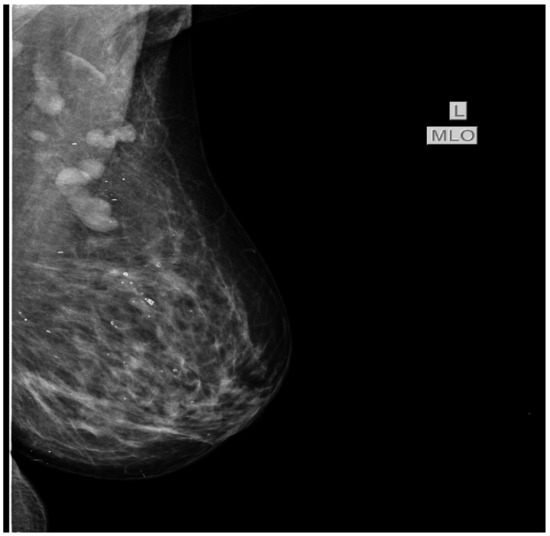

In July 2015 the patient was referred to our oncology clinic for management of an orbital metastasis with primary breast cancer. She was in a good general health status, had normal weight and Eastern Cooperative Oncology Group (ECOG) 0. Clinical examination of the breasts revealed a palpable mass of 2.5/3 cm in size in the left upper outer quadrant and the enlargement of ipsilateral axillary lymph nodes (cN1). In the upper internal quadrant of the right breast a tumor of 1.5/1 cm with a firm consistency and a smooth surface is palpated. The value of carbohydrate antigen 15-3 (CA 15-3) was 53 U/mL (normal values < 28 U/mL). Subsequently, standard mammography and bilateral breast echography were performed. Mammography showed in the upper external quadrant of the left breast a density asymmetry, with multiple micro-calcifications and associates multiple axillary adenopathies without the visualization of the fatty hilum (Figure 3). On the upper internal quadrant of the right breast, mammography also revealed an oval shaped image with benign characteristics suggestive for a fibroadenoma (Figure 4). Breast ultrasound revealed the left breast discerned an inhomogeneous hypoechogenic area of 23/22 mm, imprecisely delimited in the upper external quadrant and ipsilateral adenopathies. Breast imaging reporting and data system score (BIRADS) was 5 for the left breast, suggestive of malignancy. For the right breast, the BIRADS score was 2 with a suggestive aspect of mammary fibroadenoma. The established clinical diagnosis for this stage was: left superior external quadrant breast cancer cT2 cN1 pM1 stage IV.

Figure 3. Bilateral mammography shows in the upper external quadrant of the left breast a density asymmetry, with multiple microcalcifications and associate multiple axillary adenopathies without the visualization of the fatty hilum.